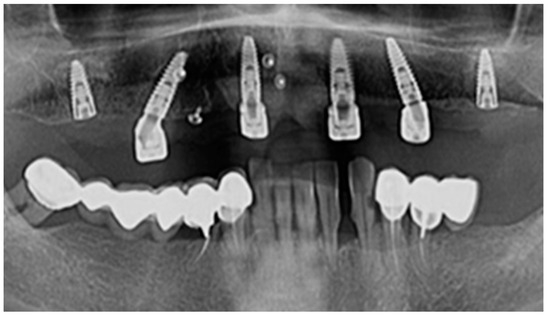

The follow-up of the patients was made at 1 month, 3 months, and 6 months from the moment the suture threads were removed. Retro-alveolar and OPG X-rays were performed in isometric and orthoradial incidences using the Belot method [16] (Figure 3). In cases where any kind of suppurated complications occurred less than a month after the insertion, the dental implant was removed.

Figure 3.

Radiological images of clinical cases during the follow-up period.